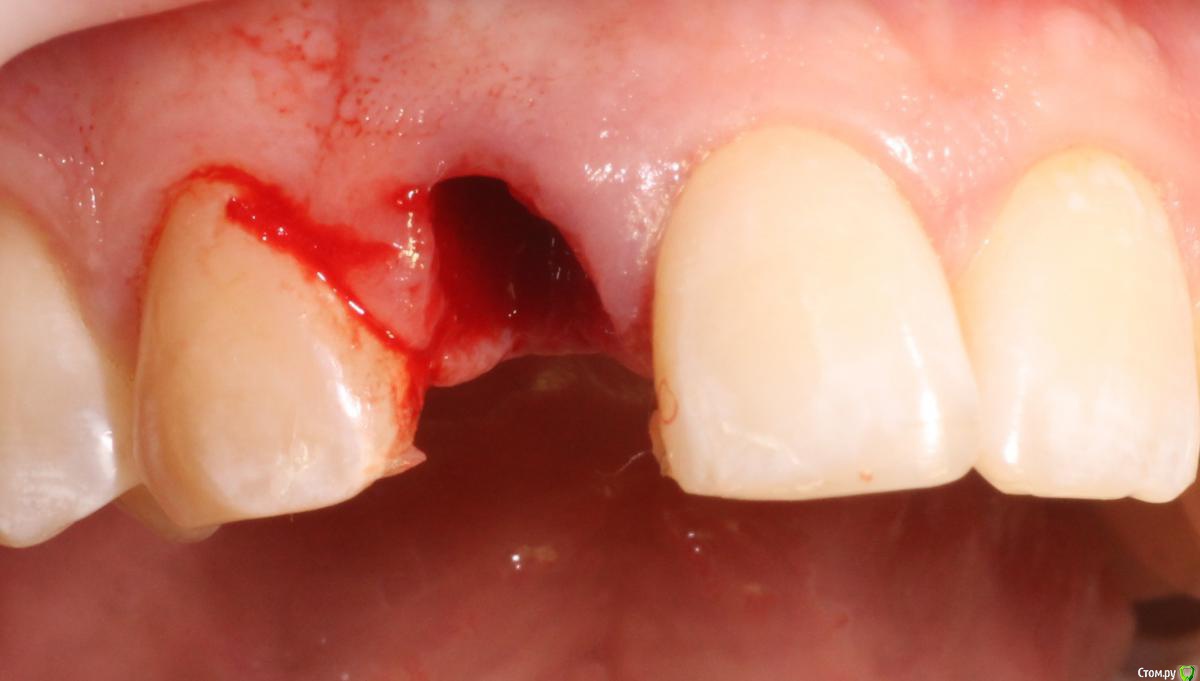

MenshikovDV Опубликовано 2 апреля, 2015 Поделиться Опубликовано 2 апреля, 2015 (изменено) Зуб 1.2 отлом коронковой части зуба, на период ожидания приема у хирурга и ортопеда (2 дня) приклеен к соседям. Вся процедура в одно посещение. Где-то часа два. Я ортопед, хирургия не моя, фото мои Изменено 2 апреля, 2015 пользователем MenshikovDV 19 Ссылка на комментарий